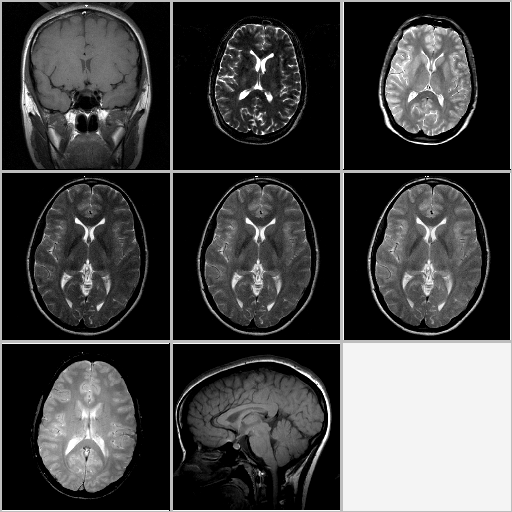

These images were acquired using a state-of-the-art 3T medical imager at the St.Joseph hospital, London, Ontario, in 2000. Courtesy of Dr. Paul Picot.